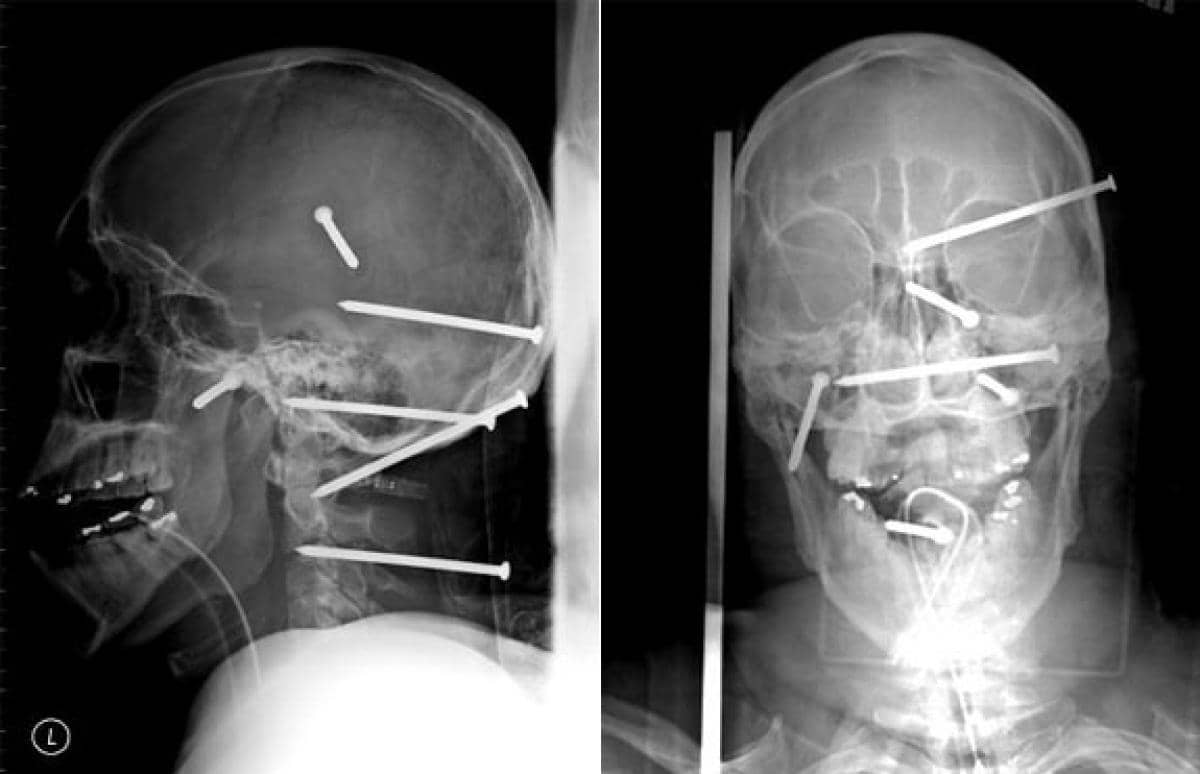

14. Isidro Mejia

Mejia, 39 tahun, saat itu sedang bekerja di atas atap rumah baru yang sedang dikerjakan oleh krunya. Tiba-tiba ia kehilangan keseimbangan dan menjatuhi rekan kerjanya yang sedang menggunakan penembak paku. Ketika ia mendarat di rekannya, secara gak sengaja 6 paku tertembak ke tengkoraknya. 3 di antaranya menusuk otaknya, 1 menusuk tulang belakangnya dan 2 lagi ditemukan menembus mukanya. Walaupun begitu ia tetap bertahan hidup.